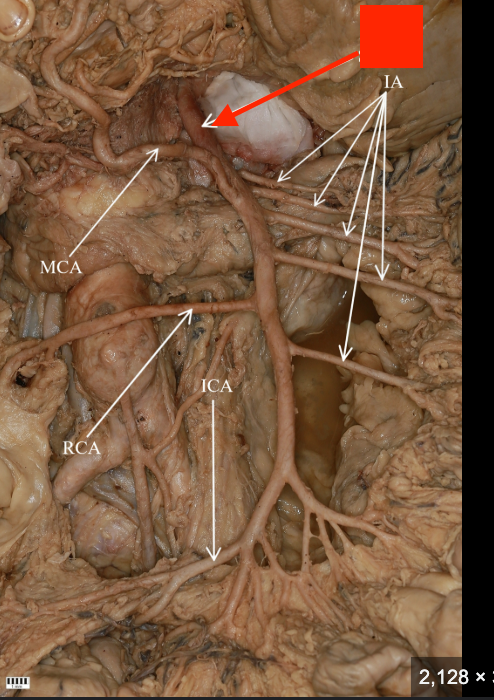

GI anatomy pin test

128 Terms

celiac trunk

left gastric artery

splenic artery

common hepatic artery

hepatic artery proper

gastroduodenal artery

superior mesenteric artery

inferior mesenteric artery